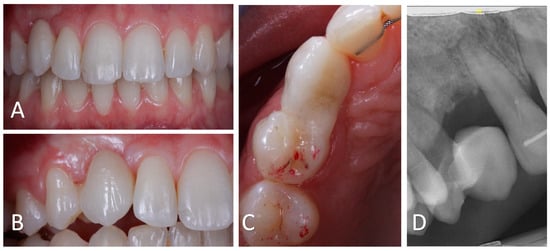

Figure 11. Follow-up at 19 months after surgery. (A): Intra-oral frontal view showing satisfactory aesthetics of the bonded bridge. The black triangle between # 13 and # 12 appears to be smaller. (B). Intra-oral lateral view displaying the healed gingiva in the cervical embrasure on both to the cantilever bridge. (C): Occlusal view of # 13 showing the absence of static or dynamic occlusal charge. (D): Sagittal CBCT radiograph showing bone preservation and partial replacement of the residual root by bone.

After 19 months of prosthetic rehabilitation, the patient is satisfied with the aesthetics of the prosthetic restauration (Figure 11). The cantilever bridge is well integrated both biologically and aesthetically. In addition, the prosthetic canine is free of occlusal charges (Figure 11). The periodontium is healthy and the bone appears to have been preserved (Figure 11). The black triangle between # 12 and # 13 appears to have decreased (Figure 11).